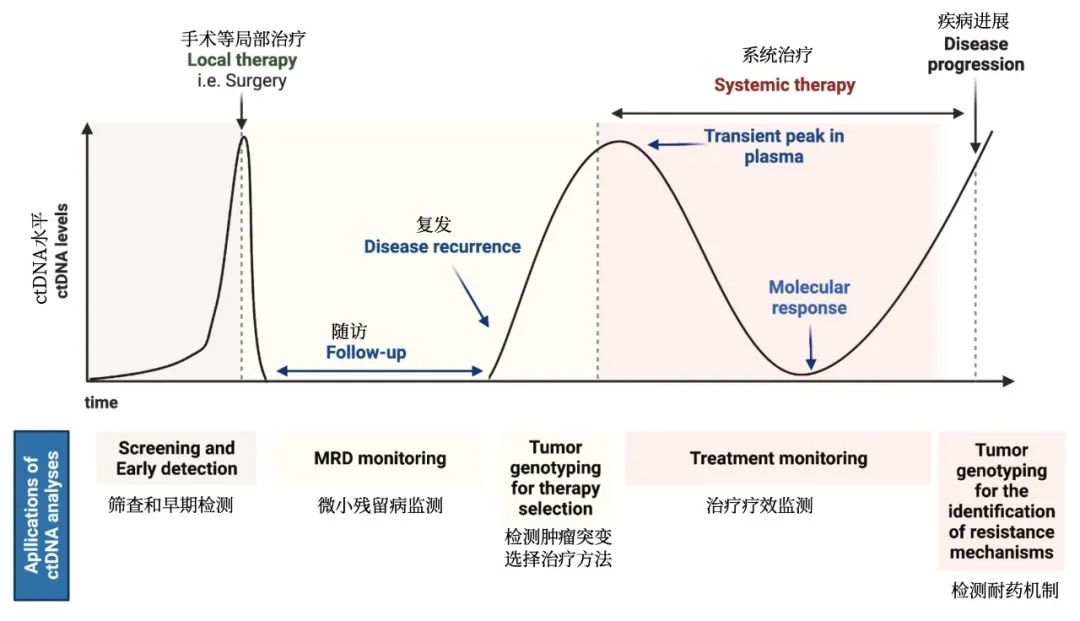

没想到我这么大岁数,切掉一个肺叶的十年后,再次做这么复杂的手术还这么顺利。 D大爷今年72岁,10年前曾行左肺上叶切除+淋巴结清扫术,手术标本病理为腺癌,术后给予了四次化疗。当时的胸部CT即可见右肺上叶小结节影,术后定期复查,病灶缓慢增大,一度略有缩小,此后再次逐渐增大。结合患者一直随访的影像学资料,杨如松院长考虑为右上肺新发恶性肿瘤。 2015年胸部CT 2020年胸部CT 虽然患者及其家属手术的意愿非常强烈,但此手术难度较高,原因在于: 1.患者年龄较高,手术风险大。 2.患者10 年前肺癌手术切除左边肺的一半,肺功能丧失较多。 3.病灶在右上肺的深部,切除有一定的难度。 为了保证患者术后的生活质量,我们不能够做肺的楔形切除这样的简单肺手术,而需要行肺段的切除。 EDDA重建提示病灶位置深 如果放在以前该患者就只能做做放化疗等保守治疗了。幸亏南京胸科医院目前引进了各种国内乃至国际上的先进技术。 如EDDA术前三D成像技术;只有单一3cm长切口的单孔胸腔镜技术;近红外荧光镜肺段、亚肺段精准定位技术等。 有了这些技术,杨如松院长心中有了底气。杨院长根据病人的情况设计手术方案,尽量减轻手术创伤,让接受第二次肺部复杂手术的高龄病人能够耐受,并且在术后能够顺利恢复。 根据术前EDDA三维重建,患者进行了单孔荧光胸腔镜S1a+2a切除术,术中先用ICG反染法确定段间面,再用膨胀萎陷法印证段间面,这保证了手术切除的精准性。 患者术中快速病理为贴壁型腺癌,这也印证了杨如松院长术前对患者肺结节良恶性的判断。 术后5天,D大爷非常顺利的出院了。出院前开心的窦大爷连声感谢杨如松院长:没想到我这么大岁数,切掉一个肺叶的十年后,再次做这么复杂的手术还这么顺利,谢谢、谢谢! 基本情况